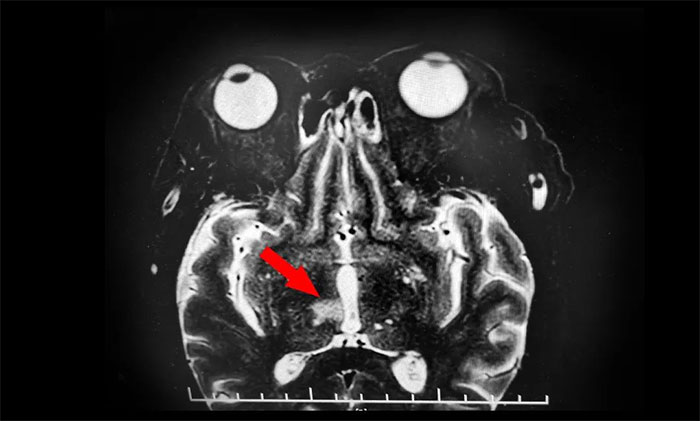

眼眶核磁共振檢查發(fā)現(xiàn)端倪

山重水復(fù)疑無(wú)路,柳暗花明又一村。隨后,為了進(jìn)一步明確患者視力不清及動(dòng)眼神經(jīng)損傷性質(zhì),張靜波主任決定為患者行眼眶核磁共振檢查。最終,患者眼框核磁發(fā)現(xiàn)端倪;颊哐劭艉舜呕貓(bào)患者腦干、丘腦梗塞灶。

再次行MR頭顱MRI平掃+增強(qiáng)+DWI+MRA,提示腦干、右側(cè)丘腦及雙側(cè)大腦半球白質(zhì)多發(fā)梗塞灶及缺血灶(中腦及右側(cè)丘腦梗塞急性期),右側(cè)大腦后動(dòng)脈狹窄,右MCA-M1段狹窄。至此,該患者雙側(cè)動(dòng)眼神經(jīng)損傷原因診斷明確,病因?yàn)橛覀?cè)中腦梗死所致,責(zé)任血管為右PCA-P1的狹窄致中腦旁正中動(dòng)脈閉塞,為動(dòng)眼紅核綜合征,導(dǎo)致同側(cè)動(dòng)眼神經(jīng)麻痹伴對(duì)側(cè)肢體共濟(jì)失調(diào),同時(shí)累及右丘腦旁正中動(dòng)脈。

▲ 眼眶核磁發(fā)現(xiàn)腦干、丘腦梗塞灶